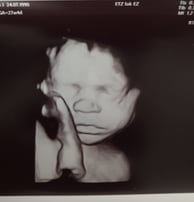

Welkom op de website van Charlie, die zijn geheimen met vrienden en familie wil delen. Een bijzondere tijd nadert!

Ontdek de wereld van Charlie en zijn bijzondere weg naar volwassenheid.

Een speciale plek voor Charlie.